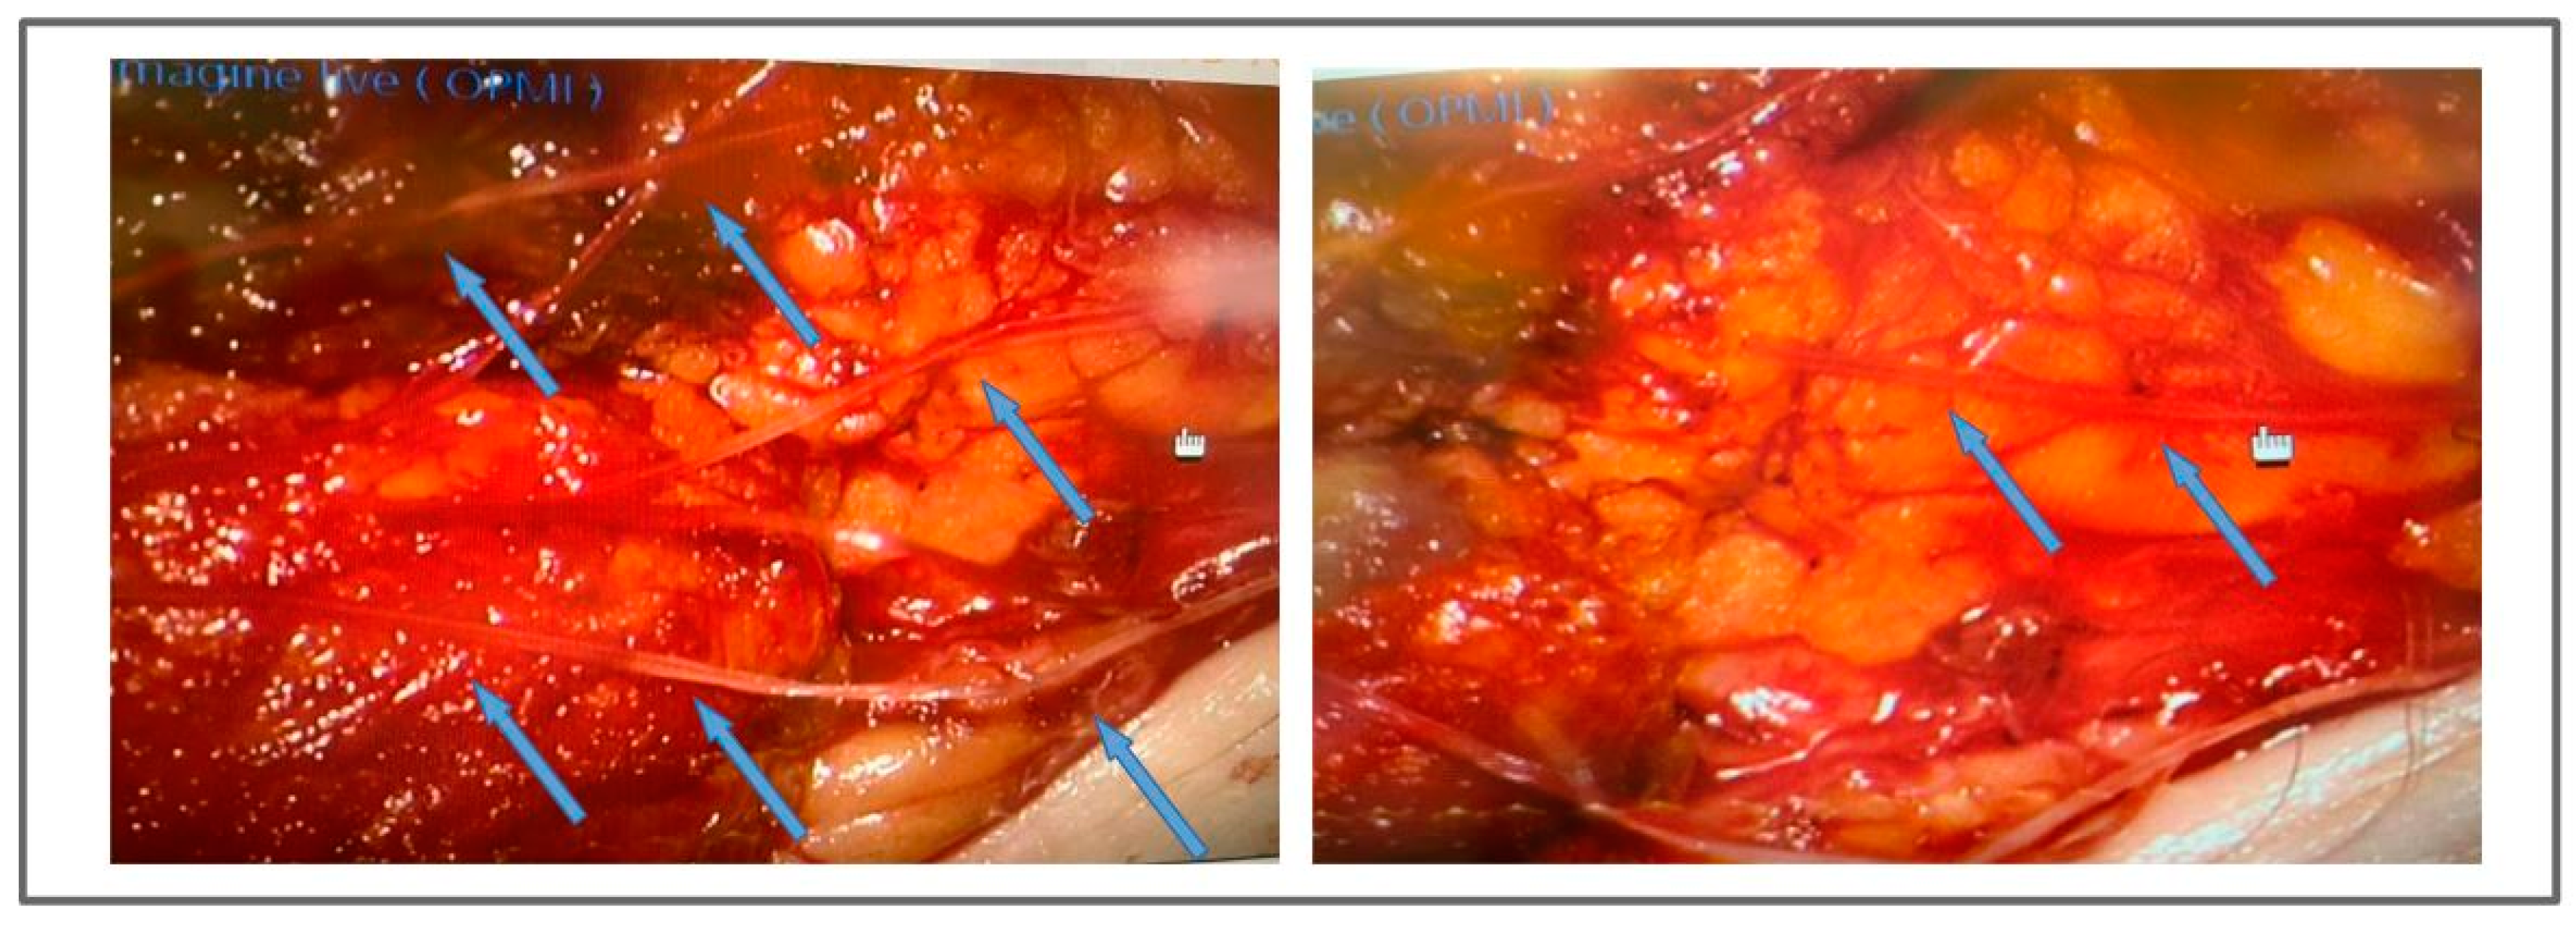

Figure 3.

Surgical images showing the positioning of the collagen scaffolds. The figures show a surgical flap for the lymph node transplant, placed in the left groin. The scaffolds, indicated by the arrows, are BioBridgeTM mesh ribbons that were inserted in the surgical site to favor the growth of lymphatic vessels. The newly developed lymphatic vessels can use collagen fibers as a scaffolding to grow.